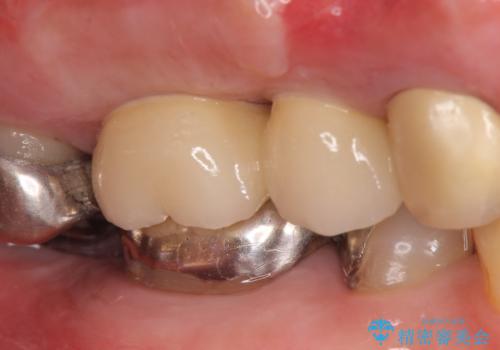

右上の567ブリッジを外したところ、右上5は歯根破折により保存不可能だったため、右上56部にインプラントを埋入し欠損補綴を行いました。

また右上5部に関しては抜歯時に歯槽堤保存術(抜歯窩に人工骨の填入を行う手術)を行い、骨の欠損を最小限に止めています。

カスタムアバットメントは患者様それぞれの歯茎に合わせて製作されたオーダーメイドのアバットメントです。

既製のアバットメントに比べ適合がよく、高い清掃性を誇ります。